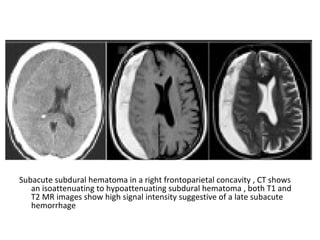

5-Mass Effect :